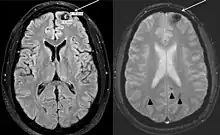

The person's largest cavernous malformation is shown in the left frontal pole. This lesion has classic signs of hemorrhage (white arrows). More lesions compatible with cavernous malformations in other areas of the brain can also be observed (arrowheads). Poland syndrome.[2]